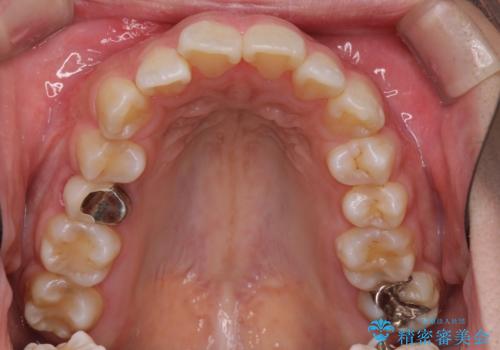

- 歯並びがガタガタなのと、口が閉じずらいのを主訴に来院されました。

上下左右の歯を1本ずつ、合計4本抜歯して、ワイヤー矯正を行うこととなりました。

右上の歯は、歯並び的には前から4番目の歯を抜歯したかったのですが、5番目の歯がすでに治療してある歯でしたのでこちらの歯を抜歯しました。

これにより少し治療期間が延びてしまいましたが、健康な歯を残すことができました。